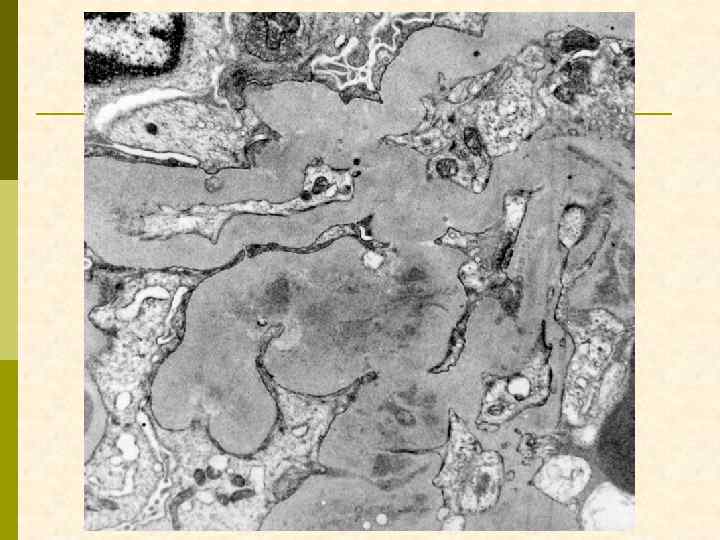

В. Клинический случай № 10152 Н. , 1971 г. рожд. , в конце февраля 2005 г. появились отеки, которые вначале были непостоянными, однако 1 марта из-за удушья был экстренно госпитализирован в городскую больницу. Диагностирован нефротический синдром (общий белок 45 г/л, холестерин 12, 8 м. М/л, в моче белок 2, 0 -2, 9 г/л, эритр. – густо. АД 160/100 мм рт. ст. Через 10 дней переведен в ЛОКБ. Hb 144 г/л, СОЭ 62 мм/ч, общий белок 51 г/л, альбумин 17 г/л, холестерин 11, 7 м. М/л, креатинин 0, 11 м. М/л, протеинурия 12, 7 г/сут. УЗИ: большие эхоплотные почки. Подтверждено носительство вируса гепатита С, выявленного в 2002 г. Выполнена диагностическая нефробиопсия. Лечение (начато до получения результатов нефробиопсии): преднизолон per os 120 мг ч/д, циклофосфамид 200 N 10, и. АПФ, симптоматические средства.

мембранозная нефропатия + ФСГС, коллаптоподобный

Заключение по ЭМ p В нефробиоптате один частично склерозированный клубочек со значительно утолщенной капсулой, в которой имеются массивные отложения электронно-плотных депозитов и скопления коллагеновых волокон. В неизмененных зонах клубочка гломерулярная базальная мембрана (ГБМ) капилляров неравномерно утолщена с интрамембранной локализацией электронноплотных депозитов. Субэпителиальных и субэндотелиальных депозитов мало. Более массивные депозиты расположены в умеренно расширенном мезангиальном матриксе. В ГБМ коллабированных капилляров обнаружены депозиты смешанного характера с микролипидными включениями. Цитоплазма подоцитов с умеренным набуханием при незначительной микроворсинчатой трансформацией и со слияние малых ножек. HIV-ассоциированные тубулоретикулярные включения обнаружены в цитоплазме многих эндотелиальных клеток гломерулярных капилляров.

субэндотелиальные плотные депозиты, в том числе резорбированные

депозиты в мезангии и в ГБМ, тубуло-ретикулярные структуры в эндотелиоците

тубуло-ретикулярные структуры в эндотелиоците